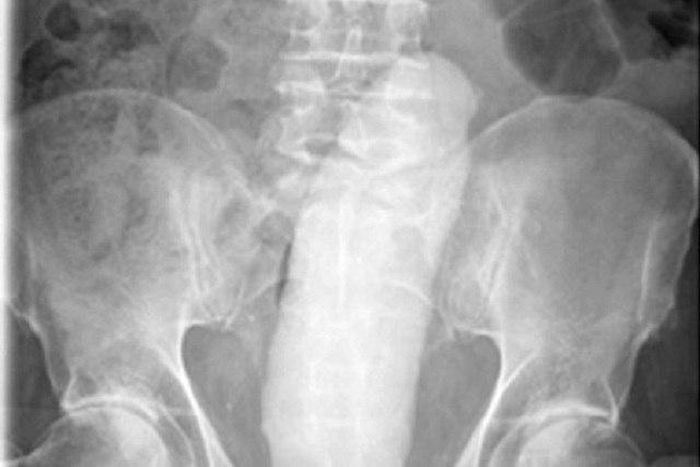

The scanned image of thee dildo in the man's rectum

A 68-year-old man who was giving himself anal sex with a sex toy had to undergo surgery to remove the dildo after it stuck in his anus.

A 68-year-old man in Dublin, the capital of Ireland, who pleasured himself with a sex toy had to undergo an emergency surgery to remove the item after it got stuck in his anus.

According to the International Journal of Surgery Case Reports, the man was using the dildo for sexual gratification when it slipped and went into his rectum.

The pensioner had to be rushed to the Mater Hospital where doctors spent 10 hours trying to remove the 23cm sex toy.

After the doctors failed to remove the toy, they gave the man a general anaesthetic so they could successfully extract the dildo using forceps.